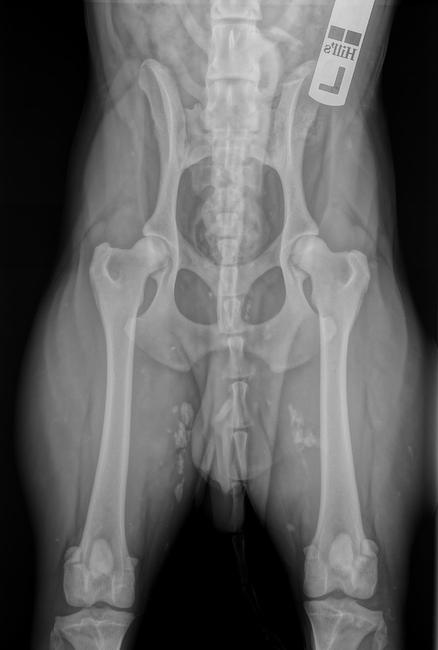

Eazy:

bij Eazy zijn de knieen wel ingedraaid maar ook die ligt echt scheef...

hij ligt wat scheef. Maar als je kijkt naar de gaten van de heupen zijn deze even groot (en dat is niet zo als hij scheef zou liggen). En het middelpunt van de heupkoppen ligt bijderzijds zo te zien mooi binnen de kommen.